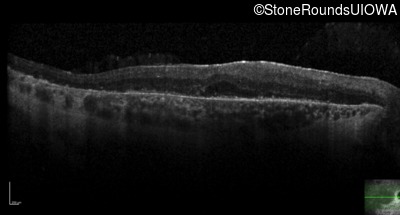

Optical Coherence Tomography - Left - 20/40 -1

Exemplar / OCT Stack

OCT Stack